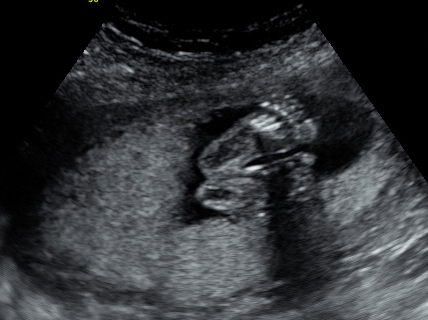

I have a great update this week because I just got back from my 20 week ultrasound and appointment with the doctor. Everything is looking great and the doctor has no concerns at all. I go back again in 4 weeks but until then I just get to enjoy feeling little one's movements. They should get stronger in weeks to come so yay for that. My DH has felt it once but since then when he puts his hands on my belly LO stops. LOL being a brat already. My bump has appeared and those who know me have said oh there is your baby bump. I've attached some pictures so please enjoy. The ultrasound tech was nice enough to switch it to 3d for the last few shots and I've attached the best one. Ahh still can't believe this is happening. I even told the doctor I keep waiting for something to happen and he said well everything looks great and will continue that way. Stupid IF brain.